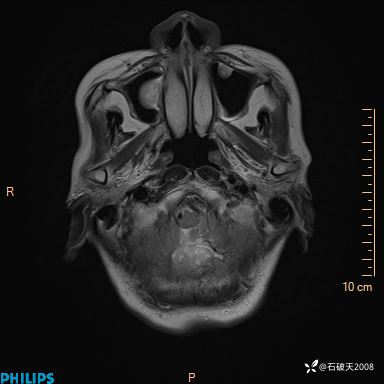

书上说这个肿瘤发生在幕下仅4.09%,你会想到它吗?(病理已公布)

FLAIR